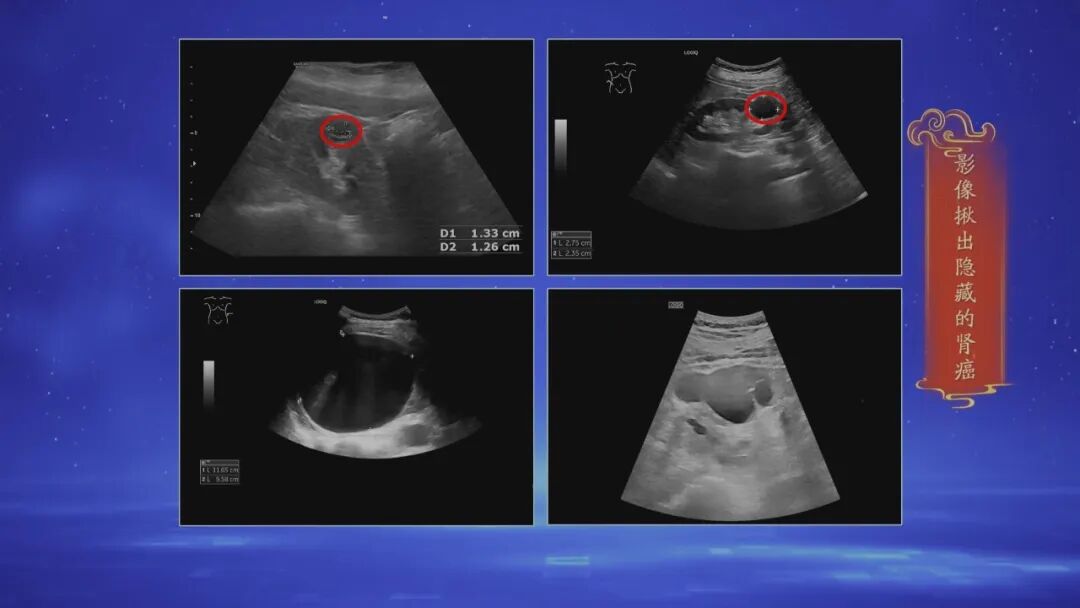

专家指出:中老年人可能2个人中就有1个人的肾脏上,有“居民”入住!虽然大多数都是“好居民”,但隐藏在其中的“坏居民”危害更大,不仅隐蔽不易被发现,更有致命危机,直接威胁到我们的生命安全!到底怎么回事?更多详情,请关注17:25播出的,北京大学首钢医院超声医学科李猛、泌尿外科汪磊两位老师为您带来的《小心会隐藏的肾癌》。

现场一位患者,肾上不仅仅有“好居民”,也有“坏居民”!“坏居民”到底什么样?通过影像能够清晰找出“坏居民”吗?肿瘤加速器又有哪些?更多详情,请关注17:25播出的《小心会隐藏的肾癌》。